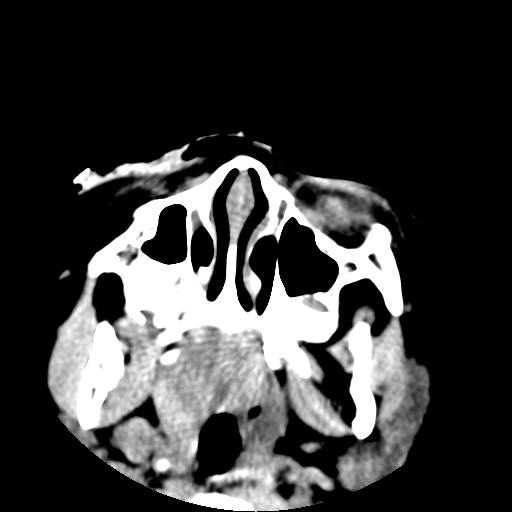

以下是引用深泽交通医院在2009-10-16 8:25:00的发言:[br]右眼环出血伴异物

以下是引用拾荒者在2009-10-17 18:38:00的发言:[br]鼻面部皮下积气,右侧睑缘及眼球壁高密度异物影,左侧眼球壁晶状体内侧缘处是圆形低密度影。低密度异物?应提请眼科医生注意。